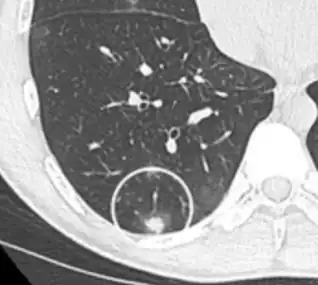

CT image showing diffuse GGOs throughout both lungs. An abscess is also noted in the right lung (screen left). - Adenocarcinoma in situ of the lung